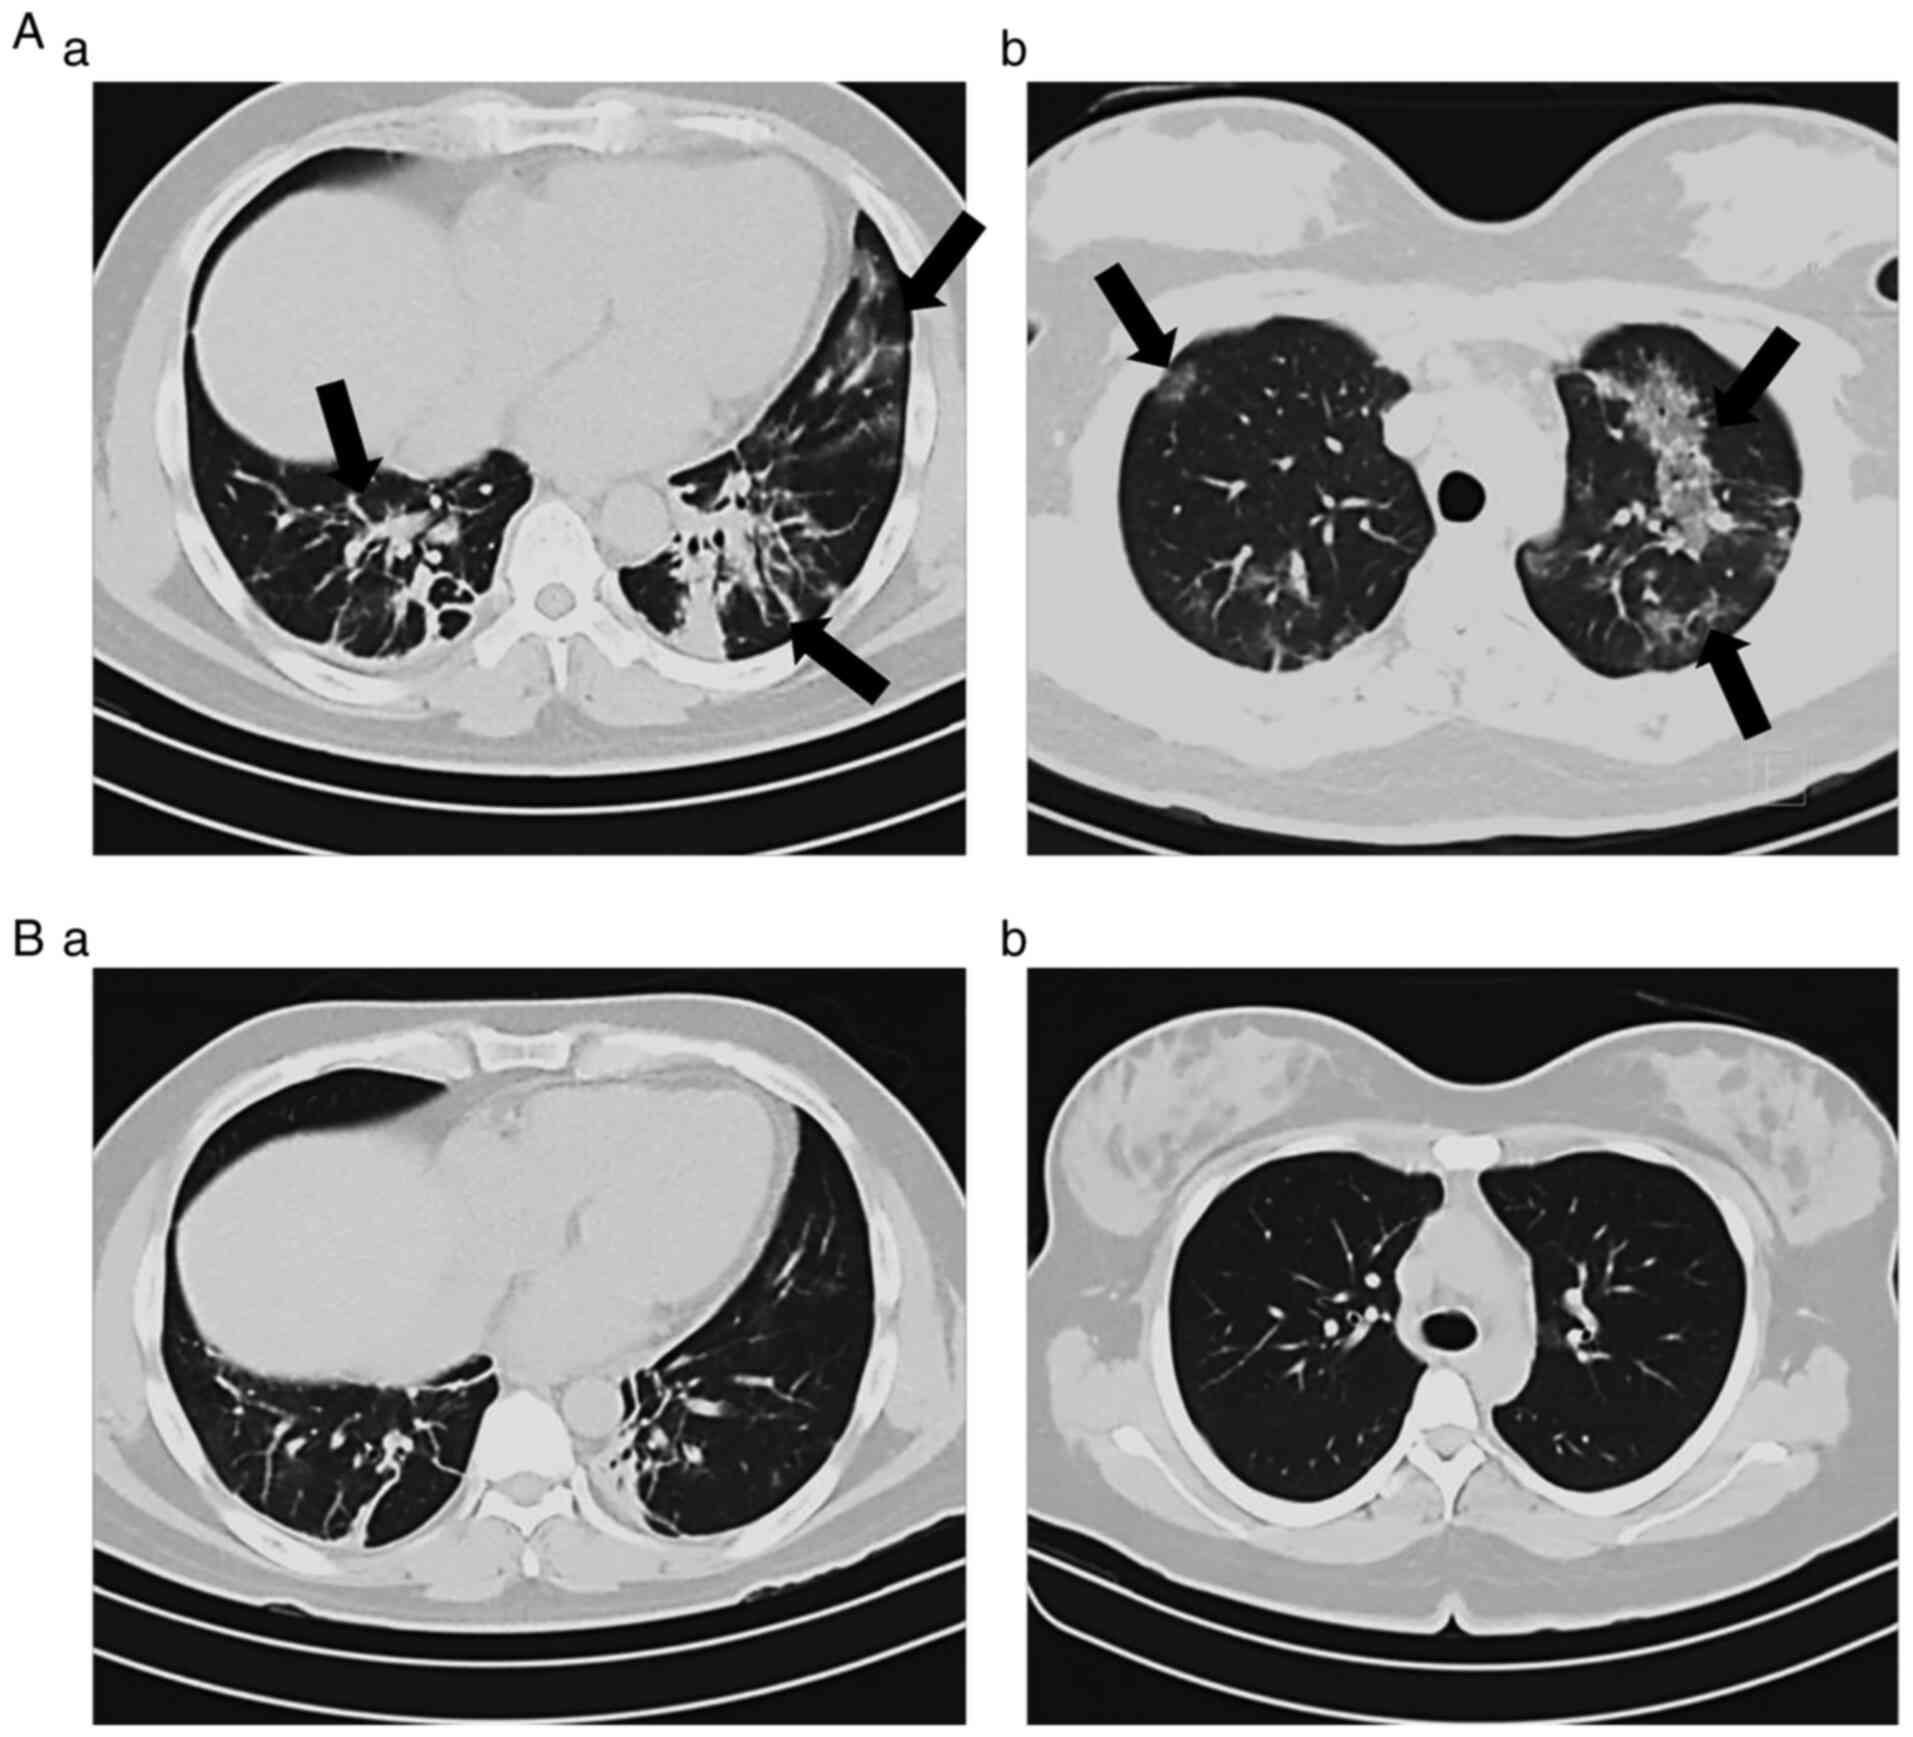

In order to determine the clinical progression and aid in the staging of the patients, the current study evaluated the oxygen saturation levels and also compared initial and end CT scans. As presented in Fig. 2, HBOT significantly increased the oxygen levels in patients with COVID-19. Of note, 12 patients had oxygen saturation levels <85% prior to treatment; however, HBOT increased these levels to >95%. On the other hand, 27 patients (75%) exhibited varying degrees of improvement in the morphological lesions shown on CT images obtained at the beginning compared with those at the end of the therapy, while the remaining 25% of the patients did not exhibit changes in their CT scans by the end of the therapy (Fig. 3).

Figure 3

Chest computed tomography images from patients with COVID-19. Two examples (A and B) of images obtained at the (a) beginning and at the (b) end of the HBOT treatment. The characteristic features observed in the tomography scans at the beginning of the treatment had changed by the end of the therapy. COVID-19, coronavirus 2019; HBOT, hyperbaric oxygen therapy.

The most frequently observed findings in CT imaging of the patients prior to the initiation of HBOT were as follows: Ground glass opacity (nebulous areas with slightly increased density in the lungs without darkening of the bronchial and vascular margins), reticular pattern (thickening of lung interstitial structures, interlobular septa and intralobular lines, manifests as a collection of innumerable small linear opacities), ‘crazy-paving’ pattern (resulting from alveolar edema and interstitial inflammation of acute lung injury, irregular cobblestone appearance) and air bronchogram [pattern of air-filled bronchi (low attenuation) on a cloudy lung fundus (high attenuation) without air]. As indicated by the arrows on the representative tomographic images presented in Fig. 3A-a and B-a, severe injury to the lung parenchyma occurred in patients with COVID-19 and these lesions were reversed following HBOT, as illustrated in Fig. 3A-b and B-b.

The effectiveness of HBOT as a supportive treatment was evaluated by examining the clinical characteristics, oxygen saturation levels and CT scan images. The majority of the patients reported a significant relief in symptomology after an average of seven sessions, with 7 patients reporting an improvement immediately after the first session, which was consistent with previous studies (7,9-12). Oxygen saturation levels also improved significantly, from 90% at the beginning to 98% by the end of the trial. The CT patterns observed in the patients with COVID-19 are in line with those reported in the literature (14). The comparison of the initial CT imaging features and those observed at the end of the study revealed a significant clearance of lung pathology, with complete reversal of the atypical findings in some patients.